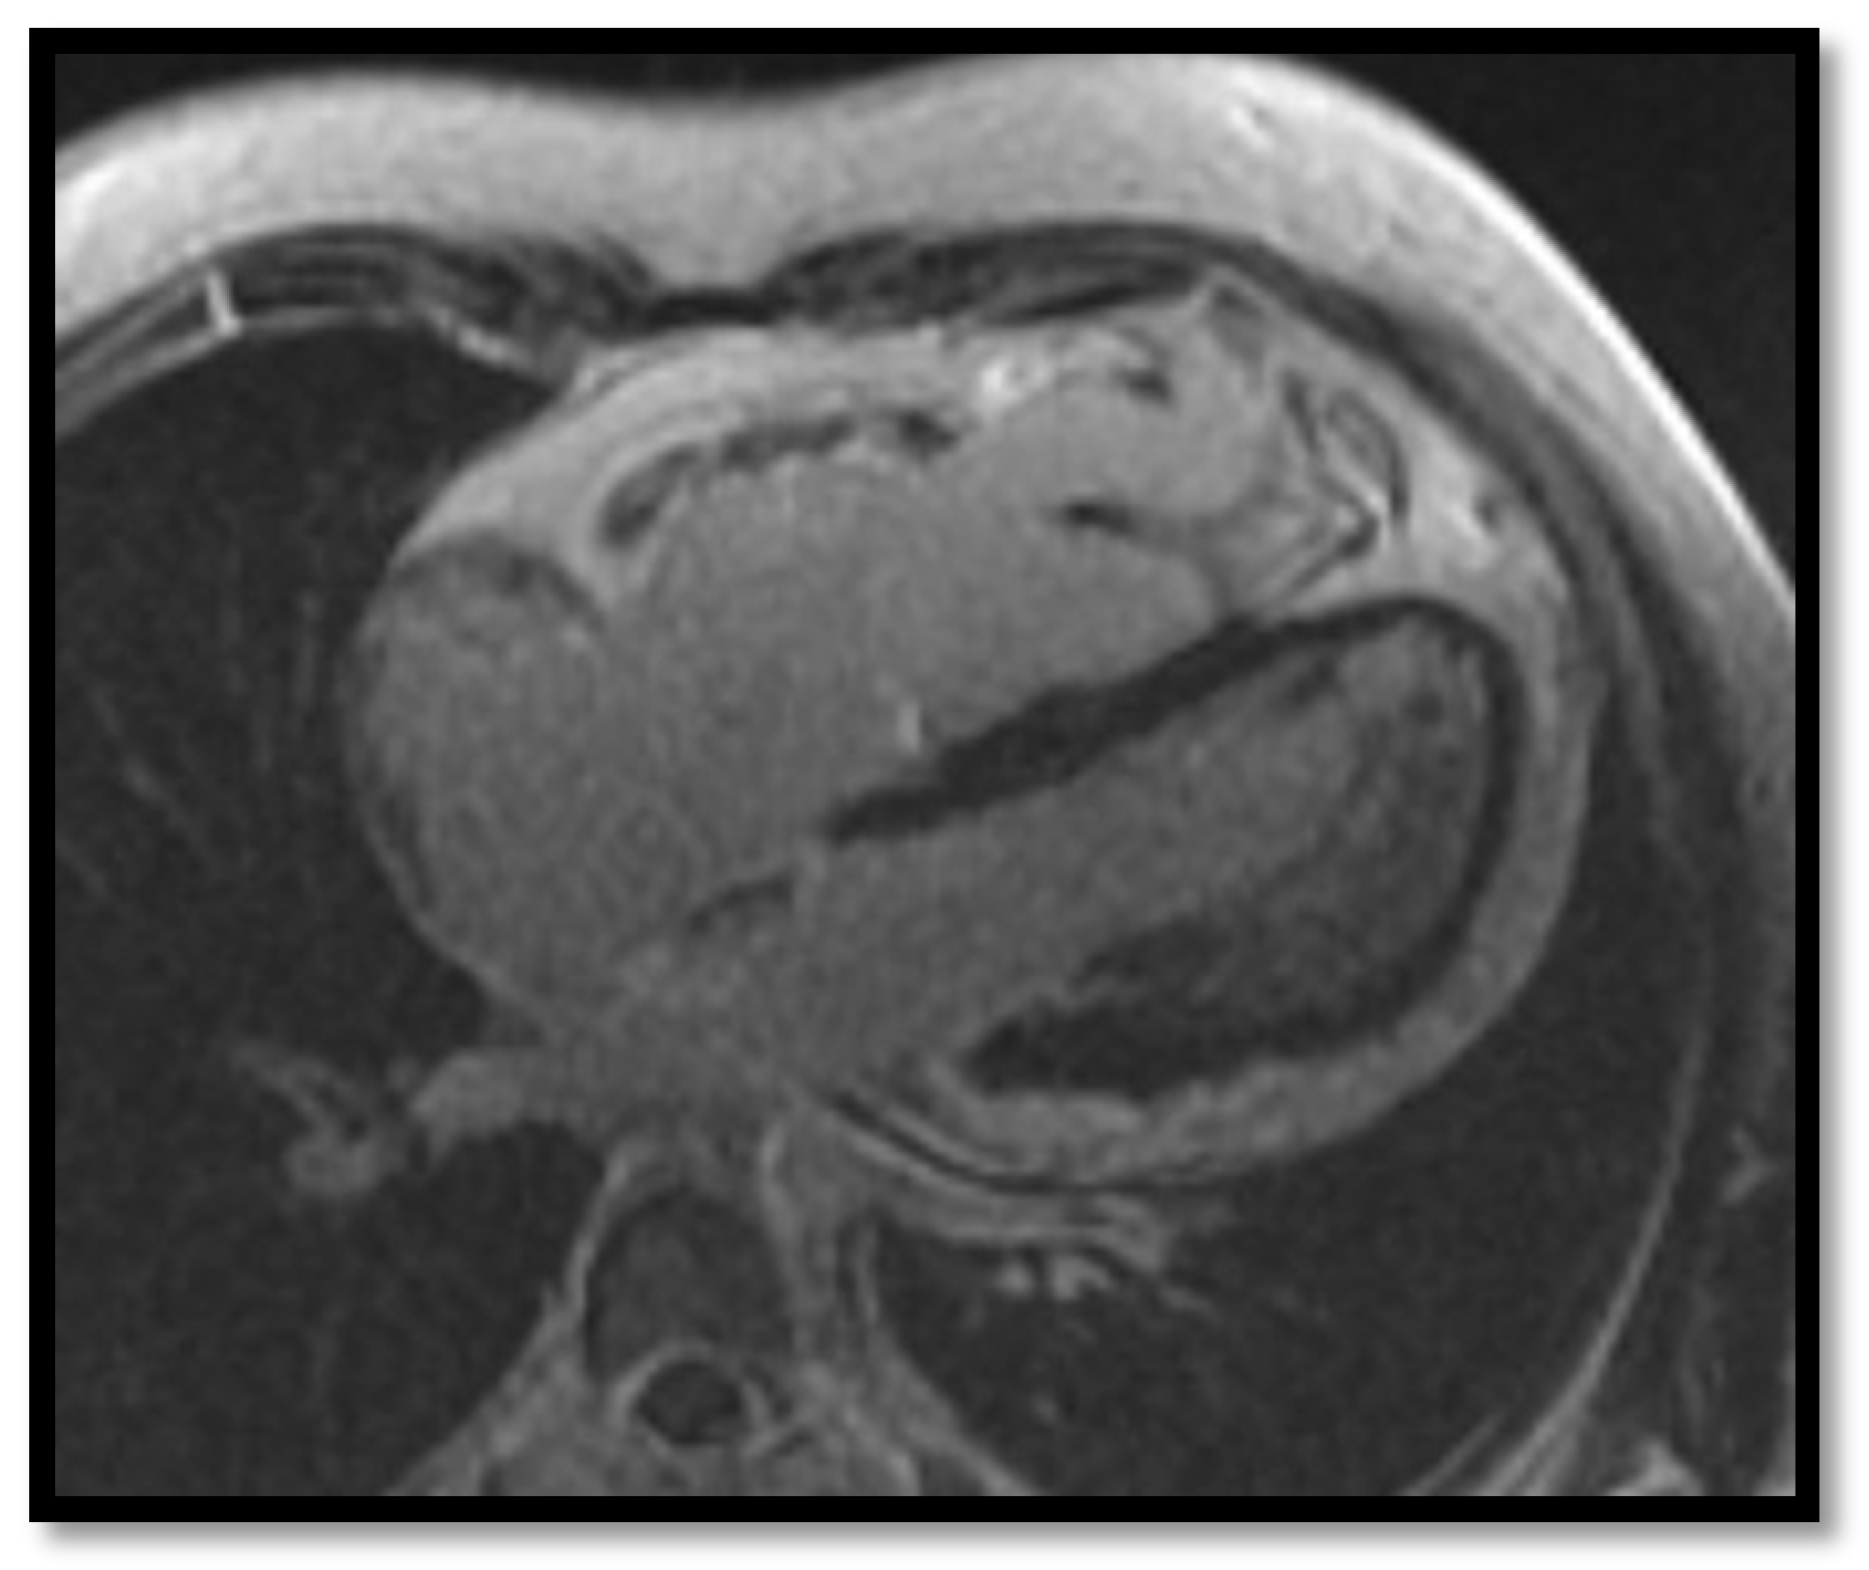

- RV dilation is also a key element for the diagnosis of ARVC. It can be segmental or global. Segmental expansion can affect only the RVOT or parts of the RV such as the basal free wall or the middle third of the free wall. It is a diagnostic criterion with high sensitivity and specificity for ARVC (Figure 3). Only the global dilation of RV is considered a diagnostic criterion for ARVC because segmental dilatation is rather difficult to interpret [12,45].

- Intramyocardial adipose tissue disposition—”obsolete”Although intramyocardial fat has long been a diagnostic criterion for ARVC, it is no longer used because other pathological or physiological conditions can lead to this appearance in cardiac MRI. In normal people, epicardial fat can penetrate to the myocardium and endocardium, with no clear demarcation between the epicardium and the myocardium, leading to misinterpreted images as ARVC. When intramyocardial fat is detected, it will be considered pathological only if it is associated with contraction abnormalities of the corresponding wall [12,45].Fat in ARVC appears as hyperintense intramyocardial signal at T1 spin-echo. Adipose tissue infiltrates mainly the RVOT, the free wall of the right ventricle, the intracavitary trabeculae, the moderating band, and the right side of the interventricular septum (Figure 4).Tansey et al. showed on autopsies of individuals without known heart disease that 85% of them had myocardial infiltrates with adipose tissue [46]. Mainly, the RVOT, free wall of RV wall, apex, and RV antero-lateral wall are affected, but these intramyocardial deposits do not change the thickness of the ventricular wall or the regional contraction. If the deposits extend from the epicardium to the endocardium, crossing the myocardium, then the ventricular wall may increase in size as a normal feature of the adipose distribution. It seems that these fat deposits in healthy people increase with age and are more common in obese people without being pathological [47].